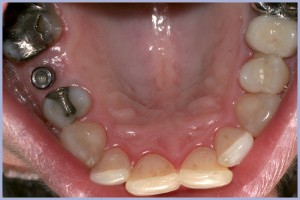

- Fig. 4 – Visione occlusale del tappo di guarigione e dei due elementi contigui (1.5 e 1.7) già protesizzati col sistema Cerec

- Fig. 5 – Immagine del collo dell’impianto ricoperto da mucosa, secondo il concetto del Platform Switching